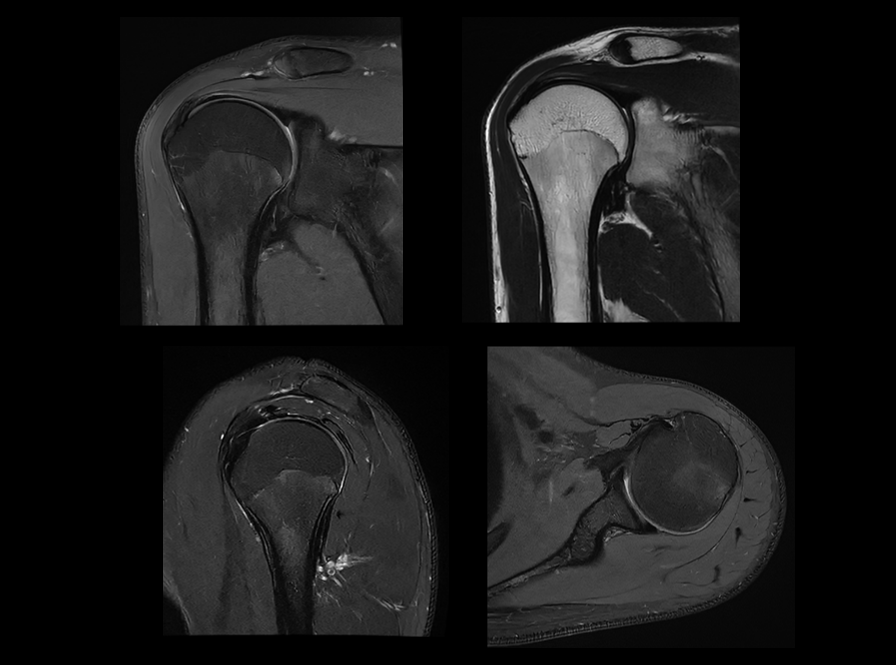

搭载uAIFI Technology技术平台,凝聚多项全球首创核心技术,全链条革新磁共振硬件、软件设计,实现系统性能、扫描智能化、成像速度与信噪比的大幅提升,同时赋予患者更舒适的检查体验,开启磁共振“类脑”时代。

在uMR 880上,我们将全身型磁共振的梯度性能推向了新的高度。更高的梯度梯度性能在弥散扫描时可以帮助用户获得更短的TE时间以提升信噪比同时得到更准确的弥散模型。

梯度功率放大器(GPA)性能是决定磁共振梯度性能的核心部件,uMR 880搭载的自主研发的超大功率梯度功率放大器为高性能梯度与梯度系统的连续稳定工作提供重要保障。